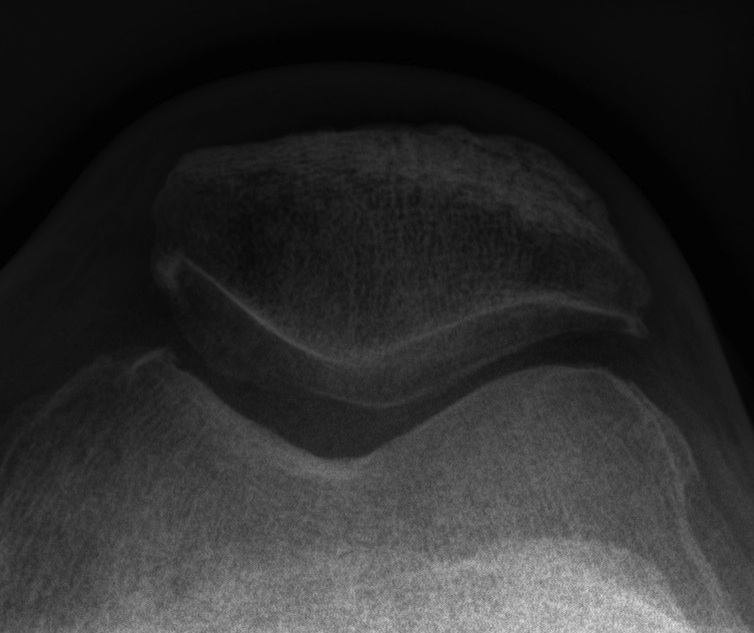

Patient 1